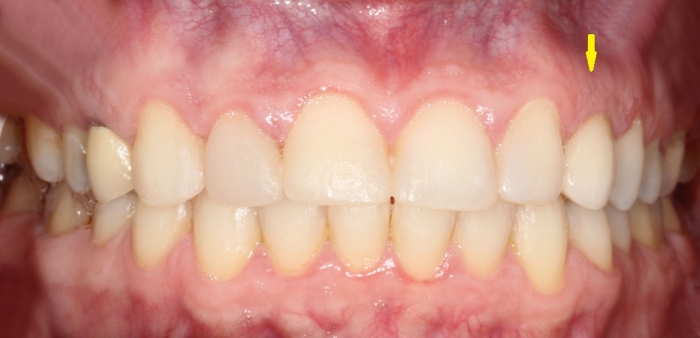

Sorriso final do caso terminado em janeiro de 2013